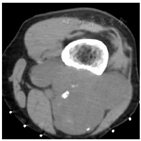

影像学检查:左膝关节计算机断层扫描(CT)显示左腘窝肌间隙内见分叶状软组织肿物,边界尚清,密度不均匀,内见结节状钙化灶,邻近股骨受侵,骨皮质变薄(图1)。左膝关节磁共振成像(MRI)显示左腘窝内一巨大不规则肿块,大小约9.1 cm×6.0 cm×10.0 cm,信号混杂,以T1加权像低信号、T2脂肪抑制序列高信号为主,弥散加权成像(b=800 s/mm2)呈不均匀高信号,增强扫描肿块明显不均匀强化,邻近股骨下端可见类似强化灶(图2)。